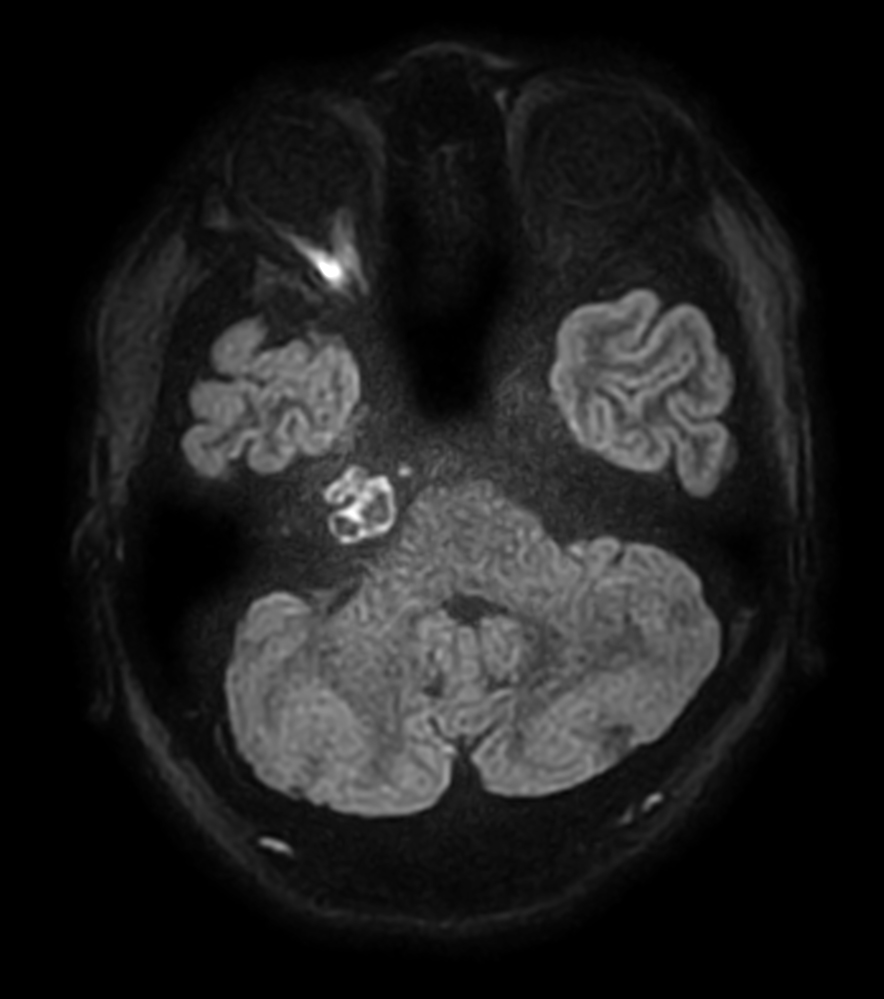

Patient with an IAC lesion. Comparing different DWI methods (EPI, TSE, ZOOM). Compressed SENSE is added to all TSE sequences to decrease scan times, thereby shortening the time the patient has to spent in the magnet. The dS Head 32ch coil is used to enhance image quality.

DWI TSE XD (b1000)